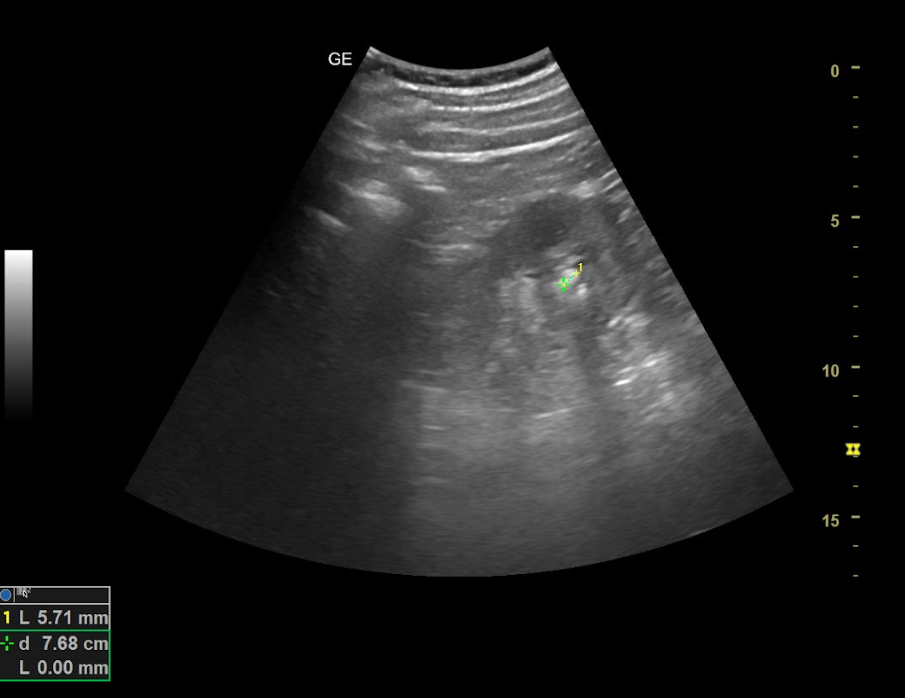

Hallazgos ecográficos

Ambos riñones son de tamaño similar considerándose normales y no apreciando hidronefrosis asociada. En el interior del riñón derecho se aprecia litiasis renal única que proyecta sombra posterior de diámetro máximo de 8,68 mm y potencial responsable del cuadro.